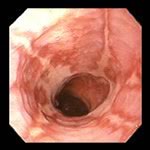

- Deglutogramma e transito esofageo con pasto di bario: evidenzia il passaggio del bolo di mezzo di contrasto dall’orofaringe allo stomaco, e l’eventuale reflusso (Figura 2), mettendo in luce anche alterazioni anatomiche (ernia iatale). Offre inoltre la possibilità di studiare il transito oltre il piloro. Il difetto dell’esame è quello di “fotografare” ciò che accade in “quel momento”, ed in questo senso la sensibilità per RGE è di fatto stimata intorno 50%. Nei bambini portatori di gastrostomia percutanea per via endoscopica (PEG) il contrasto è iniettabile attraverso il “bottone” di gastrostomia (Figura 2 bis).